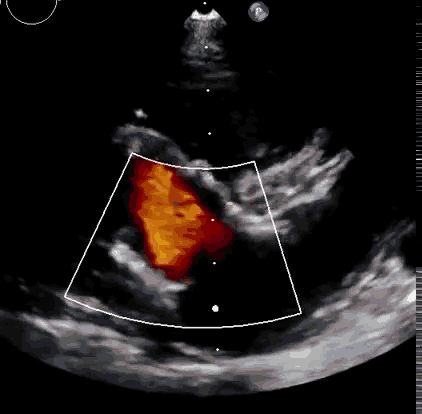

上海中山醫(yī)院葛均波院士、錢菊英院長、周達新教授、潘文志教授、潘翠珍教授、李偉教授共同完成此次臨床前研究。術(shù)后葛均波院士對Lux-Valve Plus的器械操作性能給予了高度評價,DSA和超聲影像也顯示出在本次研究中Lux-Valve Plus的安全性和有效性俱佳。

本次臨床前研究經(jīng)右側(cè)頸靜脈置入LuX-Valve Plus輸送系統(tǒng)可調(diào)彎鞘管,在DSA及超聲引導(dǎo)下將人工三尖瓣瓣膜植入到原有三尖瓣位置,利用獨特的錨定技術(shù)將人工瓣膜支架可靠固定在預(yù)定的位置。